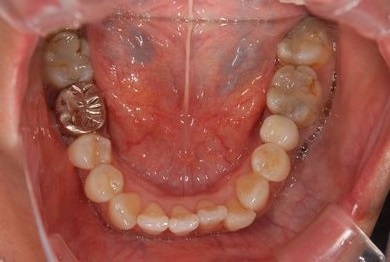

| 性別/年齢 | 女性 / 45歳 | ||||||||||||||||||||||||||||||||

| 治療方針 | 保存不能の歯を抜歯し、インプラント治療にて機能的・審美的回復を行う。 | ||||||||||||||||||||||||||||||||

| 治療内容 | インプラント1本、ハイブリッドセラミッククラウン1本 | ||||||||||||||||||||||||||||||||